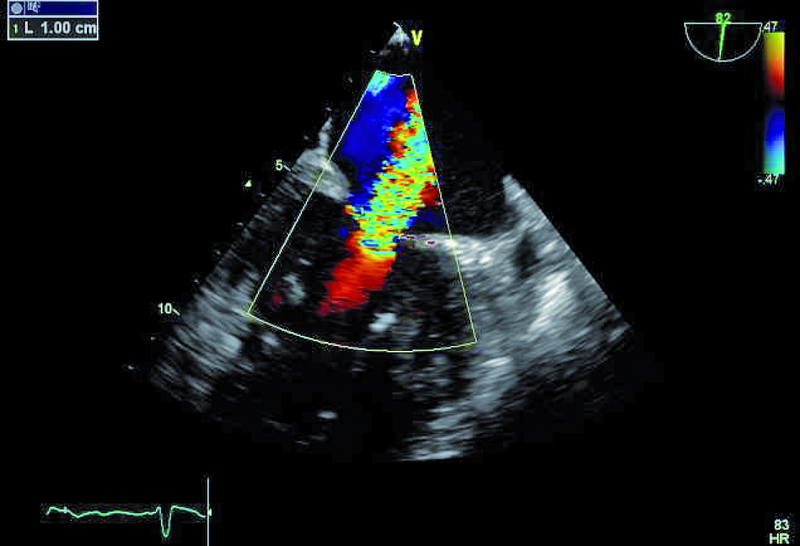

2. Istotna niedomykalność zastawki mitralnej (ryc. 2).